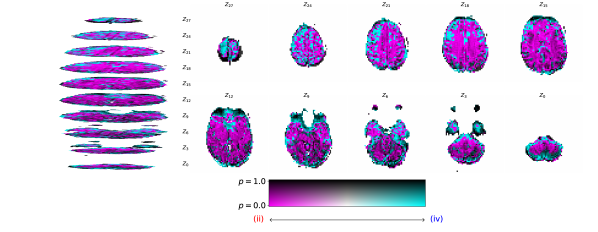

Figure 2 illustrates the distribution of residues (observed vs. estimated differences) on the fMRI volumes for the NODDI dataset. Clearly, by visual inspection, (iv) model has the darker and biggest area of shaded regions, which implies a better coverage across the brain regions and better synthesis quality. Models with topographical attention, (ii) and (iv), corresponding to Figures 2(b) and 2(d), respectively, significantly improve the synthesis, as shown by the darker and bigger areas against (i) and (iii) depicted in Figures 2(a) and 2(c), respectively. Particularly, we notice that models (i) and (iii) report difficulty in the retrieval of haemodynamical activity located in occipital and parietal lobes.

To better address which regions our baselines had more difficulty retrieving, the normalized residues were computed and are illustrated in Figure 3. Baselines – corresponding to models (i) and (ii), shown in Figures 3(a) and 3(b) respectively, which correspondingly implement a linear projection in the latent space and topographical attention –, have difficulty retrieving the prefrontal, occipital and parietal lobes, as the shade tends to a lighter grey in that region. Model (iv), shown in Figure 3(d), does not show a noticeable region with a lighter tone of grey, which implies no evident difficulty in retrieving haemodynamical activity across the different brain regions.

Figure 4 illustrates the voxel wise comparance, with statistical significance report, between (ii) and (iv). Figure 11 reports the same comparison for the rest of the models in NODDI dataset.